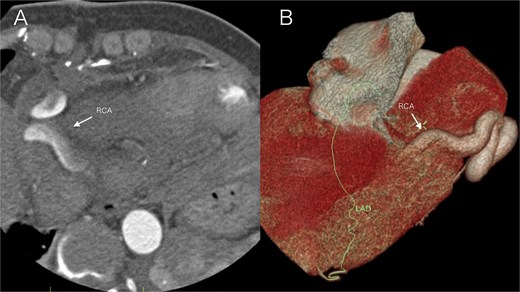

Following surgery, the patient was transferred to the intensive care unit (ICU) for further management. Upon ICU admission, the patient received continuous vasoactive agent infusion for blood pressure support, dexamethasone for edema reduction, protamine for heparin reversal, and cefazolin sodium (1 g) for antibiotic prophylaxis. Her postoperative course was stable, with transfer from the ICU on the following day. Follow-up CCTA showed no significant abnormalities (Fig. 3A and B). The patient was discharged on postoperative day 7. Upon discharge, the patient was prescribed a single antiplatelet regimen of aspirin (100 mg daily) to prevent thrombosis at the coronary arteriotomy and aneurysm repair sites, with careful consideration of bleeding risks. This medication plan was intended for adjustment according to subsequent imaging surveillance. Follow-up during the first postoperative year included scheduled CCTA and echocardiography every 3 months, alongside regular clinical visits.

Postoperative imaging on day 5 after surgical repair of a right coronary artery fistula with giant aneurysm. (A) Axial contrast-enhanced CT image at the level of the aortic root. The right coronary artery (arrow) demonstrates a normalized caliber and wall contour, with complete resolution of the preoperative aneurysmal dilation. (B) Volume-rendered three-dimensional CT reconstruction (anterolateral view). The reconstruction focuses on the course of the right coronary artery (arrow), which exhibits a smooth, uniform, and patent lumen without evidence of the previous aneurysm or fistula.